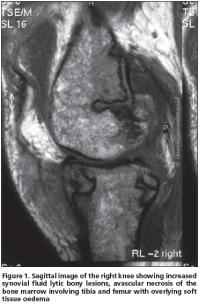

Magnetic resonance imaging of the left knee showed increased amount of joint fluid, synovial contrast enhancement, destructive changes of cortical bone in non-weight-bearing regions of the femur and tibia, and multiple foci of abnormal signal intensity. These findings were compatible with the diagnosis of fat necrosis secondary to acute pancreatitis (Figure 1). Synovial biopsy was performed endoscopically, which revealed coagulation necrosis areas, a few multinuclear cells and areas of fibrous tissue and fatty tissue.

Arthralgia (or arthritis) is listed among the presenting symptoms of this triad in one- fourth of the cases[1,3,6-8] as was also observed in our patient. Between 50% and 88% of the patients have joint manifestations at some time during the syndrome[4,9]. Although metacarpophalangeals, knees and ankles are the most commonly affected sites[4,9], any joint can be involved, mimicking rheumatoid arthritis, gout and septic arthritis. Our patient's arthritis occurred in both knees. Although systemic manifestations of this syndrome may include polyserositis, mental status changes, medullary fat necrosis of long bones and aseptic necrosis of the bones were less frequently observed[1,4,7]. As mentioned, medullary fat necrosis of both femurs developed in our patient. The radiological appearance of medullary fat necrosis is characteristic, with osteolytic lesions and motheaten bone destruction and periostitis of the tubular bones of the extremities, which correlate pathologically with areas of extensive intramedullary fat necrosis and trabecular bone destruction.